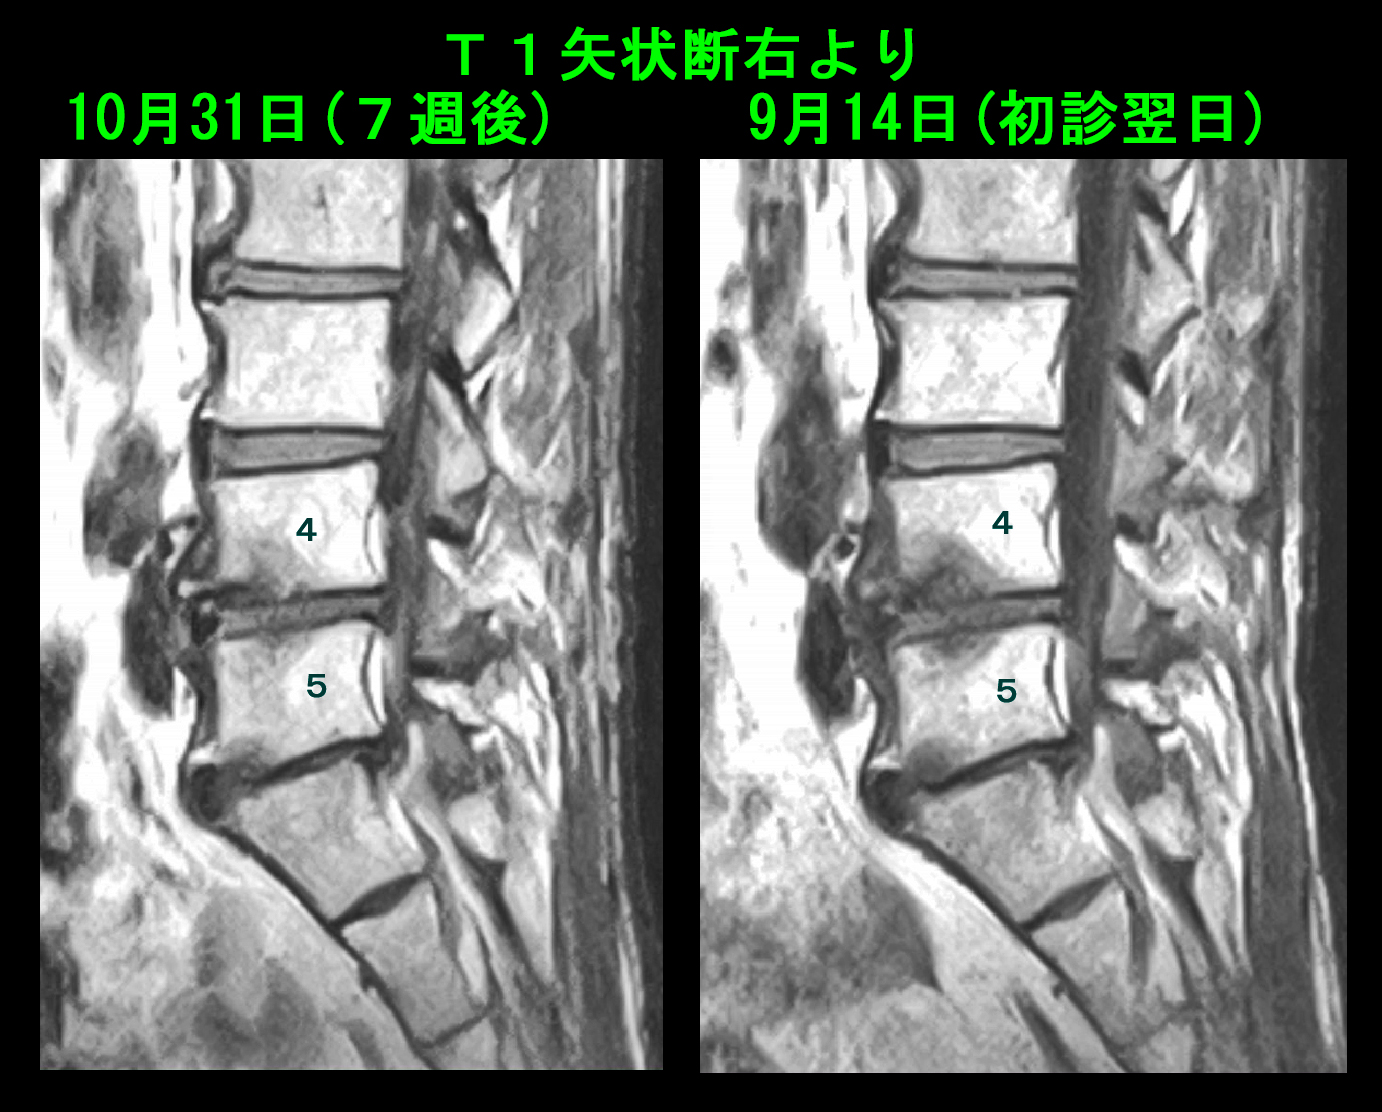

10月31日(7週後)にMRI再検査を行っています。T1の画像で変化を提示します。

71才男 MR4.jpg

L4の前方下部の右よりの黒かった骨損傷所見は正常に近い状態に改善しています。

71才男 MR5.jpg

左よりのL5後方下部の骨損傷所見はあまり改善の所見がえられていませんが、中心部の濃い黒い所見は軽減しています。